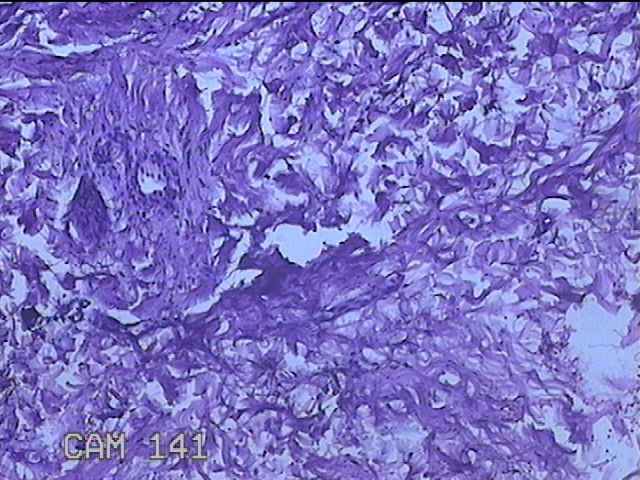

左侧臀部结节

性别

男

年龄

40岁

临床诊断

皮下结节

一般病史

发现左侧臀部结节1年余。

标本名称

大体所见

灰白粉红色组织1.3x0.8x0.3cm一块,表面带梭形皮肤1.3x0.8cm,皮下见结节1.3x1x0.7cm一个,切开结节呈实性,切面灰白粉红色,质软。

图2